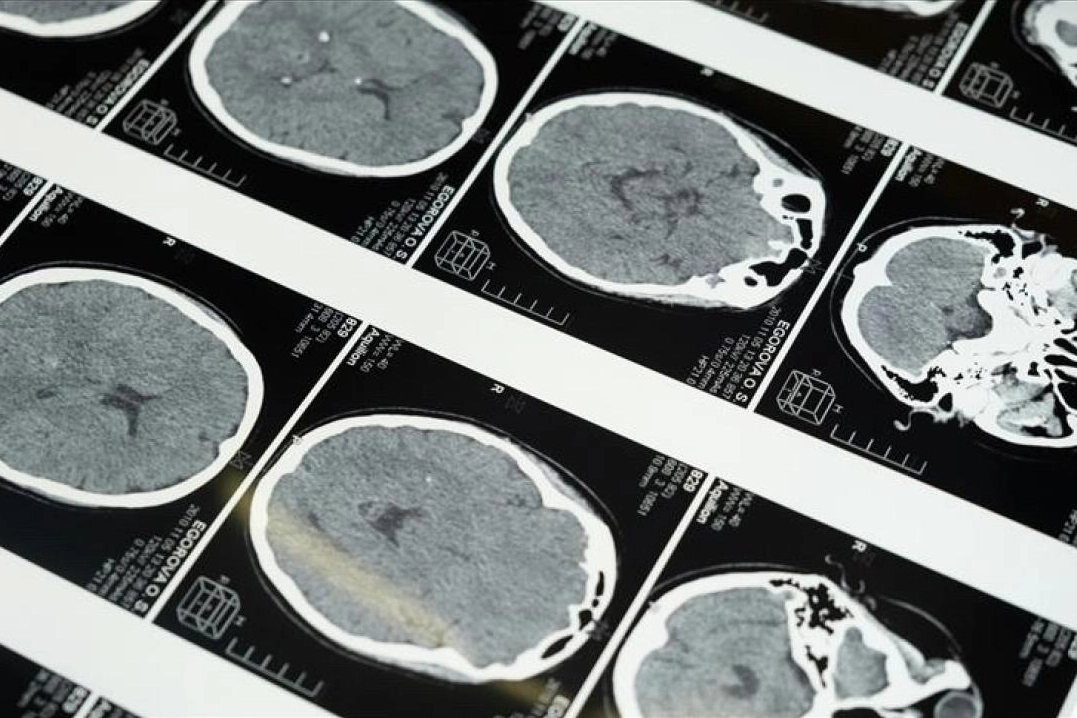

İstanbul'da düzenlenen 1. Dünya Girişimsel Nöroloji ve Nöroşirürji Kongresi'nin (WINNC 2025) düzenleme komitesinde yer alan Eskişehir Osmangazi Üniversitesi Tıp Fakültesi Nöroloji Ana Bilim Dalı Öğretim Üyesi ve İnme Merkezi Sorumlusu Prof. Dr. Atilla Özcan Özdemir, inmenin beyin damarlarının tıkanması (iskemik) ve beyin kanaması şeklinde gelişen iki türünün olduğunu söyledi.

"Özellikle pıhtıyla tıkanan beyin damarının açılmasıyla ilgili stratejiler gelişti. İnmede erken dönemde yapılan damar açma tedavileri konusunda ülke olarak iyi durumdayız. İnme tedavisinde pıhtıyla tıkalı beyin damarının anjiyo yoluyla açılması mümkün. Böylelikle hastanın 3 ay sonra, 1 yıl sonra kendi işini yapabilecek hale getirilmesi sağlanabiliyor. İnme merkezlerinde uygulanabilen bu işlemi ilk 24 saat içerisinde belirli hasta gruplarına yapabiliyoruz. İlk 24 saat çok kritik, bu müdahaleler de sadece inme merkezlerinde yapılabiliyor."